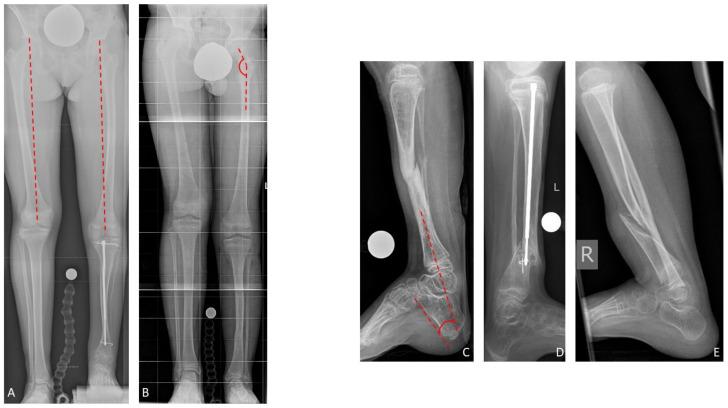

Treatment of congenital pseudarthrosis of the tibia remains a major challenge in pediatric orthopedics. Ideal timing and preference of surgical procedures are discussed controversially. A variety of reconstructive treatment strategies have been described in literature, but so far none has proven its superiority. The aim of treatment is to obtain long-term bone union, to prevent refracture, and to correct angular deformities and leg length discrepancies. This study retrospectively evaluates the outcome of different reconstructive strategies. Sixty-nine patients were identified who presented to our outpatient department between 1997 and 2019. Twenty-six of these patients underwent reconstructive surgical treatment and were included in this study. The study cohort was divided into three groups. Excision of the pseudarthrosis was performed in all patients in Group A and B, and in two patients of Group C. Group A (six/26 patients) received subsequent bone transport through external fixation maintaining original length. In Group B (15/26 patients), patients underwent either previous, simultaneous, or subsequent extrafocal lengthening through external fixation to reconstitute length. In Group C (five/26 patients), internal fixation with intramedullary nails was applied. Radiological and clinical evaluation was performed to assess bone union and complication rates. Results varied considerably between the study groups. Overall, the primary bone fusion rate was 69.2%. There were four refractures, all occurring in Group B. The long-term bone union rate without refracture was 53.8%. The overall complication rate was 53.8% and 23.1% showed persistent pseudarthrosis. Two secondary amputations were performed due to failed bone fusion. In conclusion, excision of the pseudarthrosis and extrafocal lengthening achieves a satisfying bone union rate and limb reconstruction, while bone transport does not offer significant advantages but shows higher complication rates. Intramedullary stabilization should be applied to maintain bone union, but shows lower bone union rates when used as a stand-alone treatment regimen. Regardless of the primary bone fusion rates, the probability of long-term bone union remains unpredictable.

小儿骨科中,胫骨先天性假关节的治疗仍是一项重大挑战。手术时机的选择和手术方式的偏好一直存在争议。文献中描述了多种重建治疗策略,但到目前为止,尚无一种策略证明其优越性。治疗的目的是实现长期骨愈合,预防骨折再发,并纠正成角畸形和肢体长度差异。本研究回顾性评估了不同重建策略的治疗效果。确定了1997年至2019年间在我院门诊就诊的69例患者。其中26例患者接受了重建手术治疗并纳入本研究。研究队列分为三组。A组和B组的所有患者以及C组的2例患者均进行了假关节切除。A组(6/26例患者)随后通过外固定进行骨搬运,保持原长度。B组(15/26例患者)患者通过外固定进行术前、同期或术后病灶外延长以恢复长度。C组(5/26例患者)采用髓内钉内固定。进行影像学和临床评估以评估骨愈合情况和并发症发生率。各研究组的结果差异很大。总体而言,初次骨融合率为69.2%。发生了4例骨折,均发生在B组。无骨折的长期骨愈合率为53.8%。总体并发症发生率为53.8%,23.1%表现为持续性假关节。因骨融合失败进行了2例二期截肢。总之,假关节切除和病灶外延长可实现令人满意的骨愈合率和肢体重建,而骨搬运没有显著优势,但并发症发生率较高。应采用髓内固定来维持骨愈合,但作为单一治疗方案使用时骨愈合率较低。无论初次骨融合率如何,长期骨愈合的可能性仍然不可预测。